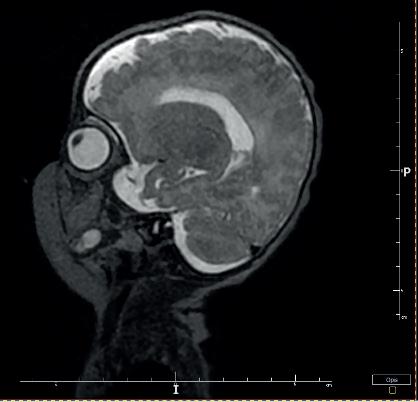

Kolejną interesującą publikacją jest artykuł Studium przypadku zespołu mozaikowej trisomii chromosomu 9 prof. Lidii Perenc z Instytutu Nauk o Zdrowiu Uniwersytetu Rzeszowskiego i współautorów. Zespół mozaiki trisomii 9 został opisany w 1973 roku przez amerykańskiego genetyka R. Haslama; w aktualnych danych uzyskanych z portalu orpha.net zaliczany jest do chorób rzadkich. W artykule omówiono przypadek kliniczny mozaikowej trisomii chromosomu 9 u niemowlęcia płci męskiej. Autorzy wskazują, że dla ustalenia prawidłowego rozpoznania należy uporządkować dane uzyskane na podstawie wywiadu, badania przedmiotowego i badań dodatkowych. W przypadku podejrzenia nieprawidłowego genotypu jako czynnika etiologicznego należy wykonać odpowiednie badania genetyczne. Warto również porównać obraz kliniczny i historię choroby pacjenta z danymi przedstawionymi w literaturze.

Another interesting publication is the article Case study of mosaic trisomy 9 syndrome by Professor Lidia Perenc from the Institute of Health Sciences at the University of Rzeszów and co-authors. Mosaic trisomy 9 syndrome was described in 1973 by American geneticist R. Haslam, and is classified as a rare disease in current data obtained from the orpha. net portal. This article discusses a clinical case of mosaic trisomy 9 in a male infant. The authors point out that in order to establish a correct diagnosis, the data obtained from the history, physical examination and additional investigations should be sorted out. If an abnormal genotype is suspected as an aetiological factor, appropriate genetic tests should be performed. It is also worth comparing the patient’s clinical picture and medical history with data presented in the literature.